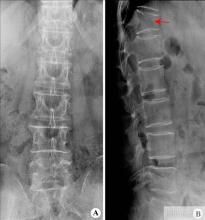

胸椎骨折(fracture of thoracic vertebrae)是以胸椎局部腫脹、疼痛,骨折處兩側肌肉緊張,不能站立,翻身困難,運動障礙等為主要表現,發生在胸椎部的骨折。並不傳染。

病因介紹 臨床表現 檢查 病情診斷 鑑別診斷脊柱骨折是骨科常見創傷。其發生率占骨折的5%~6%,以胸腰段骨折發生率最高,其次為頸、腰椎,胸椎最少,常可並發脊髓或馬尾神經損傷。脊柱骨折多見男性青壯年...

操作名稱 適應證 禁忌證 準備 方法胸腰椎骨折是指由於外力造成胸腰椎骨質連續性的破壞。這是最常見的脊柱損傷。在青壯年患者中,高能量損傷是其主要致傷因素,如車禍,高處墜落傷等。老年患者由於本...